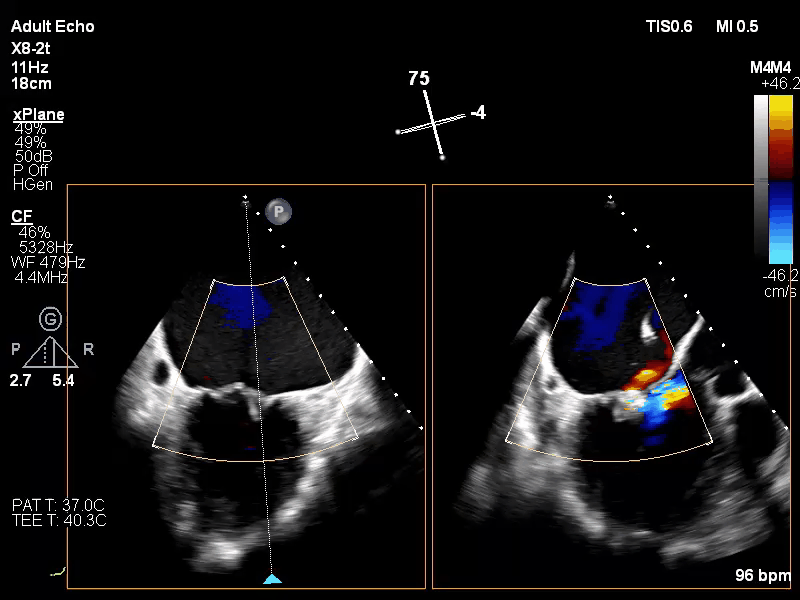

基本情况:71岁男性,入院超声心动图提示:心动过缓;二尖瓣后瓣脱垂伴关闭不全;左房大;彩色血流示,二尖瓣瓣上反流(大量),三尖瓣反流(少量);LVEF 56%。患者二尖瓣外科修复手术风险评分>6%,经多学科团队讨论建议行经导管缘对缘修复术。

Carpentier II,DMR,二尖瓣P2区域腱索断裂导致极重度二尖瓣反流,累及P1区,心脏扩大,脱垂宽度和间隙较高,瓣口面积5cm²,2区前叶长23mm,后叶长20mm。反流束来自于2区及1区,呈偏心性,沿前叶走行,EROA=0.39cm² (r=0.9cm, av=0.31cm/s, pv=4.0m/s),VC 0.83cm。PGmean 1mmHg,TR 2+。房间隔穿刺空间约5cm。

手术于全麻下进行,采用股静脉房间隔途径,房间隔穿刺后置入外径22F导管鞘及夹合器输送系统,在TEE引导下,将1枚长宽型号的KoKaClip®夹合器顺利植入到二尖瓣2偏1区,夹合器位置稳定。彩色多普勒超声未见明显残余反流,肺静脉多普勒波形由反向恢复正常。多切面证实夹合组织充分,双孔化形成,遂移除器械输送系统,移除后夹合器活动度小,手术顺利完成,患者已于近日出院,出院超声复查良好。

术前

释放后

出院复查